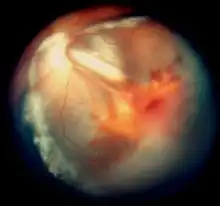

| Vitreous hemorrhage and exudative retinal detachment resembling Coats' disease in a child with cerebroretinal microangiopathy with calcifications and cysts | |

Smaller blood vessels of the retina are abnormally developed and appear tortuous and dilated to a variable extent, typically in one sector and mainly in the peripheral and temporal portions of the retina.[1][2][3][9] This is known as telangiectasia. The vessel walls are weak and leak blood plasma and lipid within and underneath the retina. This leakage can lead to exudative retinal detachment, also known as exudative retinopathy in this context. The detachment typically has a yellowish tint because the fluid under the retina contains lipid. These findings mimic Coats disease.[9] Characteristically, the abnormal vessels are localized and the retinal blood vessels peripheral to the abnormal ones seemingly have failed to develop and are thus not seen.

In some eyes, retinal vessels form small nodules on the surface of the retina, known as angiomas.[1] These can bleed and be attached to the vitreous humour. The attachment can cause traction retinal detachment.

By analogy to Coats disease, the exudative retinopathy is thought to result from breakdown of the blood-retinal barrier at the level of the vascular endothelial cell, resulting in leakage of blood plasma and lipid.[14] Macrophages then migrate into the retina and subretinal space and digest the lipid. The accumulation of the proteinaceous exudate and macrophages thickens the retina, leading to exudative retinal detachment.